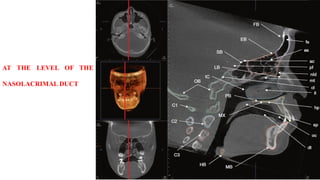

AT THE LEVEL OF THE

NASOLACRIMAL DUCT

AT THE LEVELOF THE NASOLACRIMAL DUCT